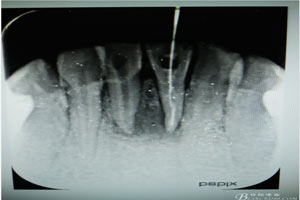

圖3.術(shù)中x線片檢查:31預(yù)備植根中1/3與根尖1/3遇阻力,根管測(cè)量無(wú)法測(cè)到長(zhǎng)度,根尖1/3牙膠無(wú)法取出。

圖4.31插入診斷絲照片